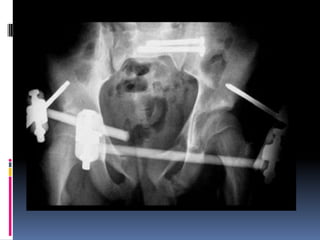

Rx AP fractura tipo B3

Varón de 59 a. caída de

caballo.

Rx del control de la

redución

movilización con el fijador

externo